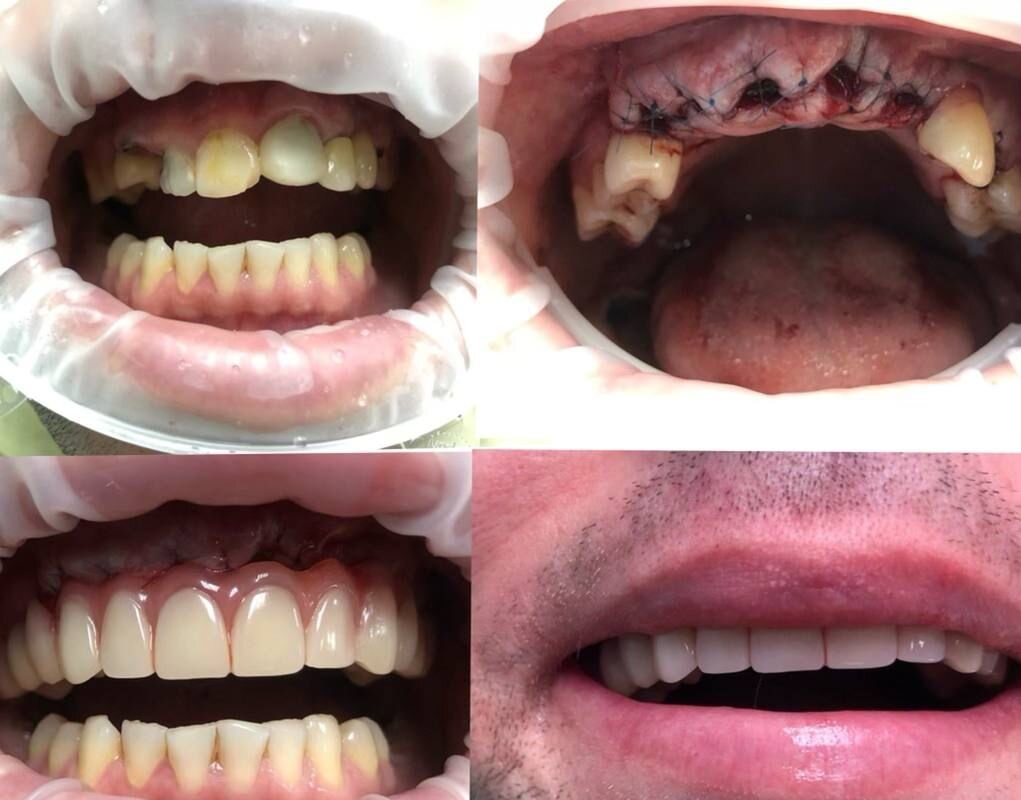

Стоматолог-ортопед, хирург, имплантолог

Синанян Хачатур Георгиевич является стоматологом-ортопедом, а также работает в сфере имплантологии и стоматологической хирургии. Хачатур Синанян в том числе делает пластику десны, уздечки губ и языка и тканей полости рта, устанавливает условно-съемные протезы, металлокерамические и безметалловые протезы, штифты, вкладки и виниры, а также выполняет несъемное и съемное протезирование зубов, микропротезирование зубов, шинирование зубов и синус-лифтинг.... Показать еще

Фото работ врача Хачатура Георгиевича Синаняна